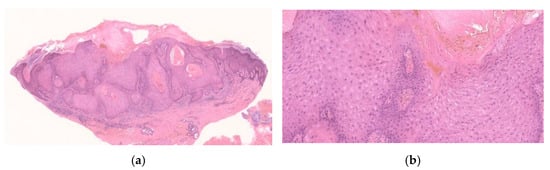

2.2. Histopathological Findings

2.2.1. Histopathological Stages

2.2.2. Mutual Findings among Stages

2.2.3. Early/Proliferative Stage

2.2.4. Well-Developed Stage